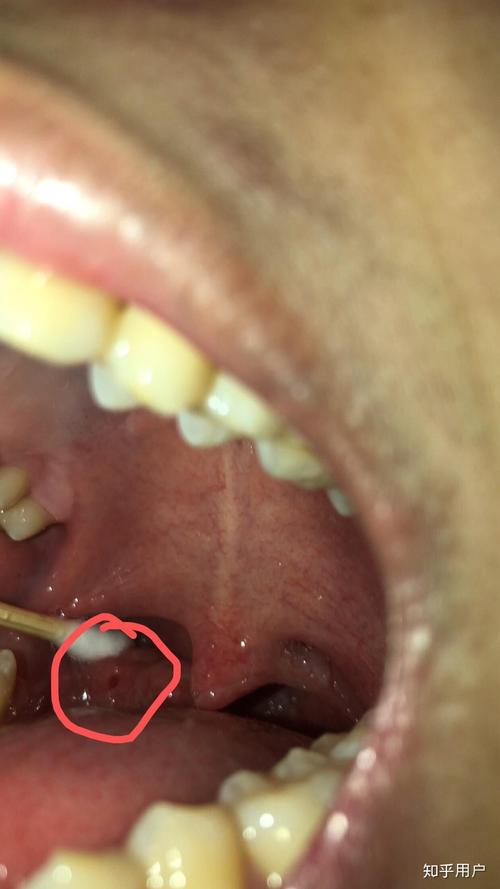

第二大元凶:可能是“发炎”的信号——扁桃体结石

如果你的黄颗粒主要出现在喉咙两侧,那就要考虑是不是扁桃体结石了。

它是什么? 扁桃体表面有许多凹陷的“隐窝”,当食物残渣、脱落的细胞和细菌在这些隐窝内堆积、钙化后,就会形成黄白色或黄褐色的、质地坚硬的颗粒状物,这就是扁桃体结石。

如何判断? 对着镜子张开嘴,压住舌头,用光照射喉咙两侧,有时能肉眼看到白色或黄色的“小石子”。